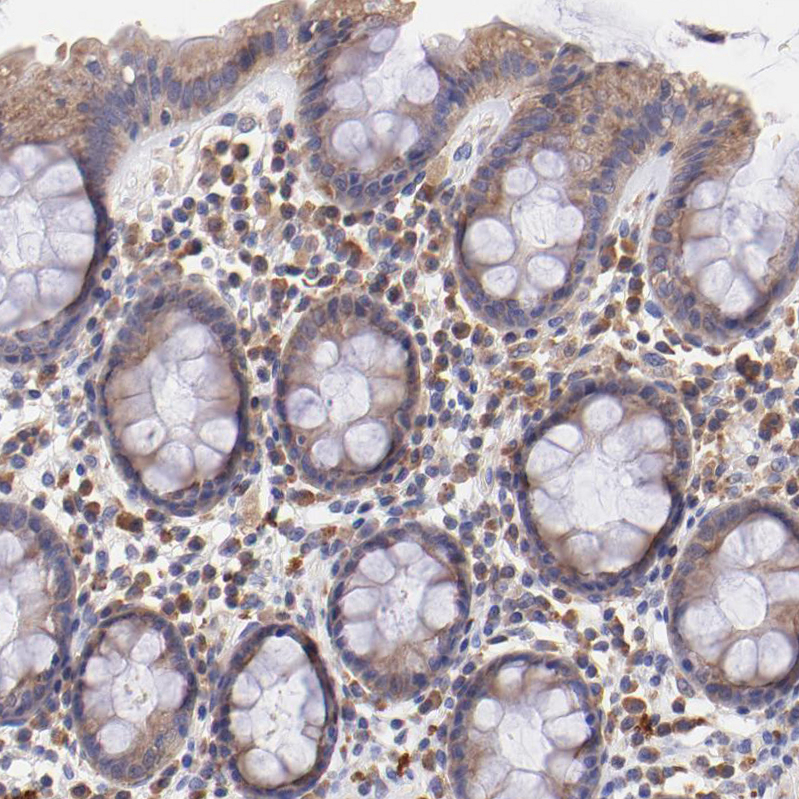

Immunohistochemical staining of human Fallopian tube shows moderate cytoplasmic positivity in glandular cells.